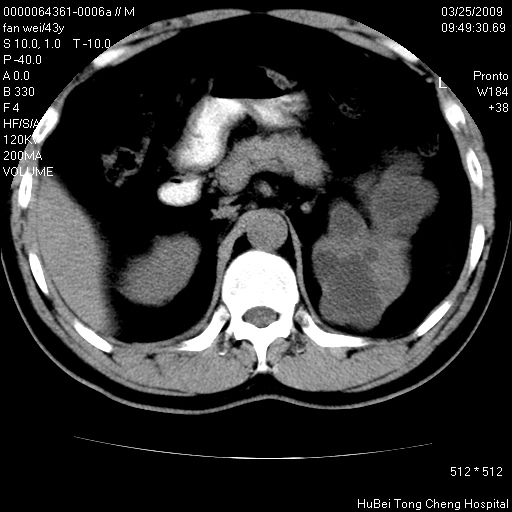

患者 男,43岁。左侧腰部不适两天。平素健康。无家族遗传病史。

腹部彩超提示:1)轻度脂肪肝。2)左肾多发囊性占位性病变;建议行进一步检查。

临床诊断:左肾多发囊性占位性病变,性质待定(多发肾囊肿?)。

双肾ct轴位平扫+增强扫描(层厚10mm,螺距1.0,重建间隔10mm),图像如下:

双肾多发性囊肿   脂肪肝

囊肿数得清,肾功能正常,考虑多发肾囊肿.另外,右肾后极突向肾周间隙的那个病灶是不是错构瘤,请楼主调窗看看.